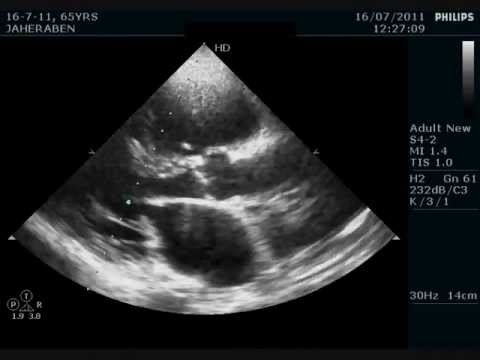

Mitral Valve Stenosis - YouTube

Http://www.remedyland.com/2012/09/mitral-valve-stenosis-mitral-valve.html Mitral valve stenosis Copyright © 2012-2013 Remedy Land All Rights Reserved. Skip navigation Upload. Sign in. Search. Loading Close. Yeah, keep it Undo Close. This video is unavailable. ... View Video

Mitral Stenosis - Sound - YouTube

This is the sound of mitral stenosis. I have kept various types for your understanding ... View Video